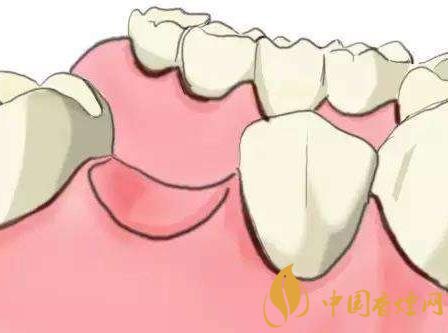

如果有烟瘾的你种了牙,你的种植医师也会严肃地督促你戒烟。抽烟可能造成种植体四周炎症产生,影响到牙槽骨吸收而造成种植失败。即使初期种植成功,长期抽烟者的种植体寿命往往也比不吸烟者短,若再加上口腔清洁不好,种植牙的使用寿命会更短。